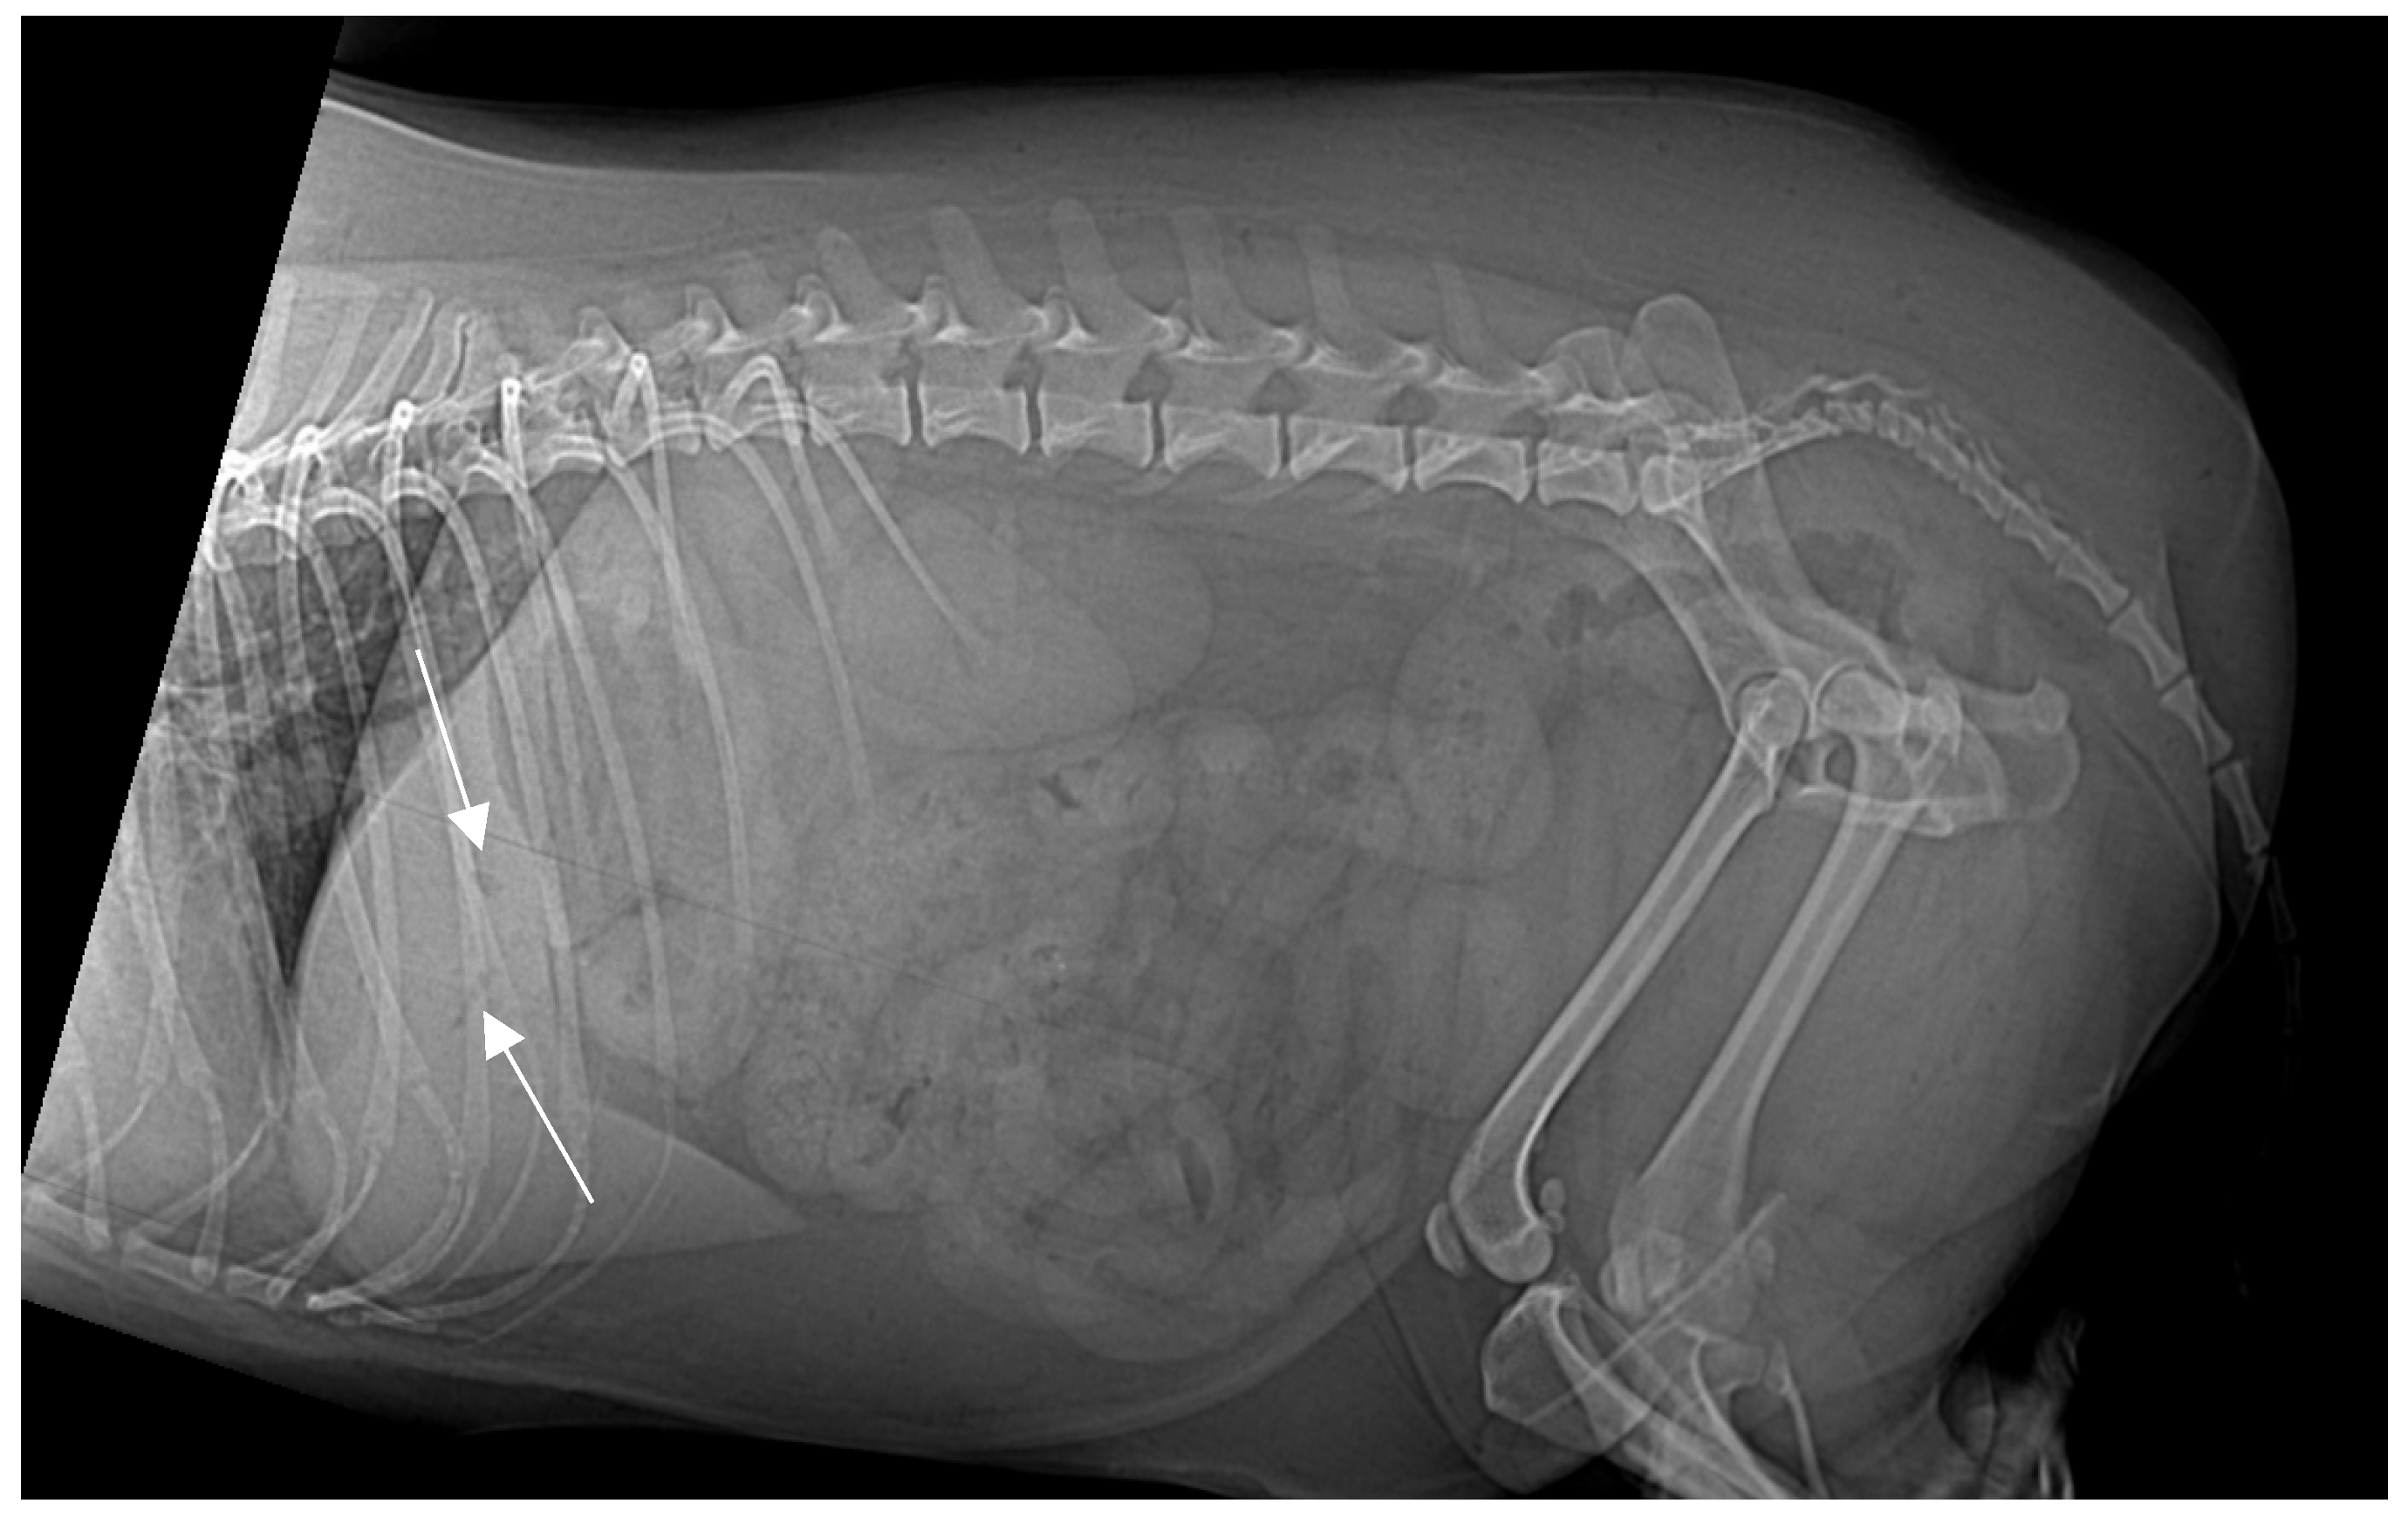

3. Results

On presentation, the patient was mildly obese (BCS 7/9) and exhibited abdominal discomfort. Initial survey radiographs showed no evidence of gastrointestinal obstruction or radiopaque foreign material. However, the lateral abdominal view revealed several small, tubular gas opacities superimposed on the caudal aspect of the liver silhouette, cranial to the stomach, and pyloric antrum, suggestive of gas within the biliary tree (pneumocholecystitis) (Figure 1).

Figure 1. Right lateral abdominal X-ray projection. No foreign bodies identified. Small, tubular gas-opacity structures (white arrows) overlap the liver’s caudal margin cranial to the stomach and pyloric antrum, suggesting pneumocholecystitis (gas within the biliary system).